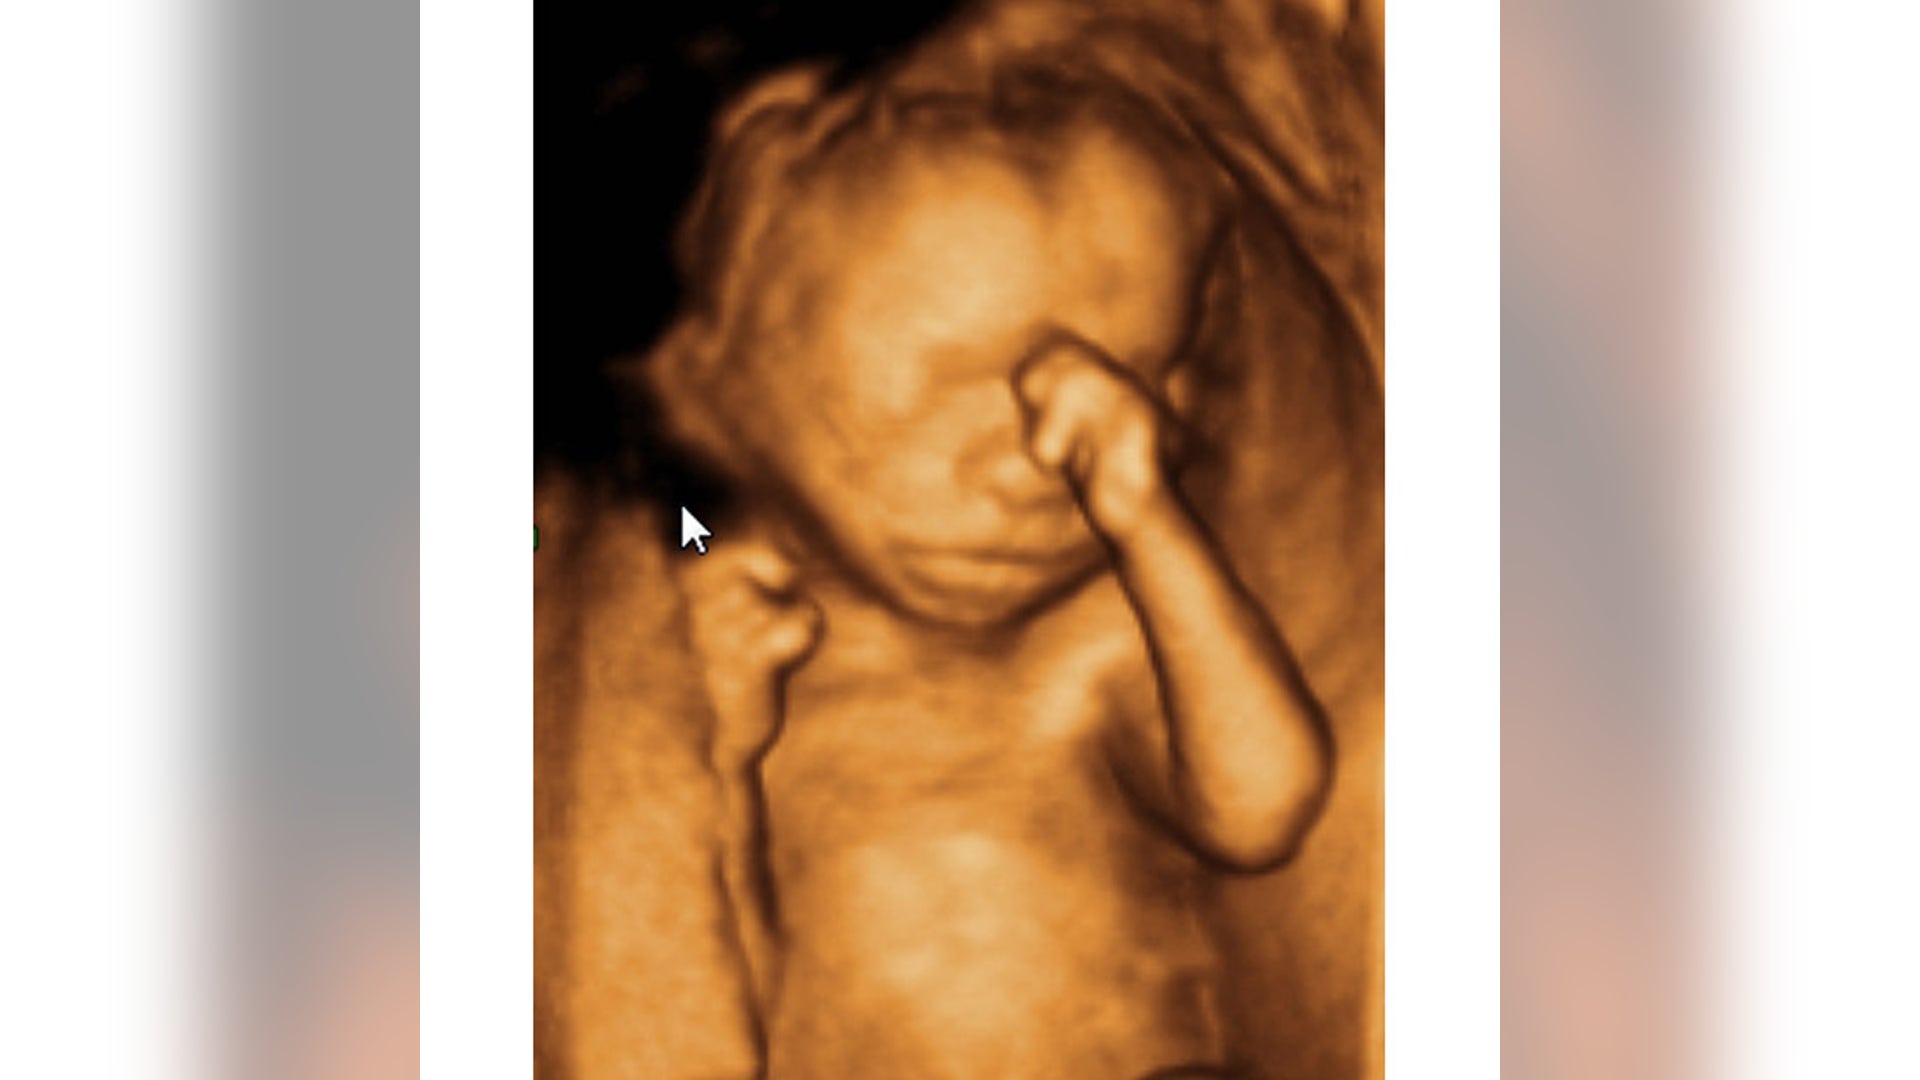

A new revolutionary scanning technique allows expectant mothers to hold three-dimensional models of their unborn children.

New Fetus Scanning Technique